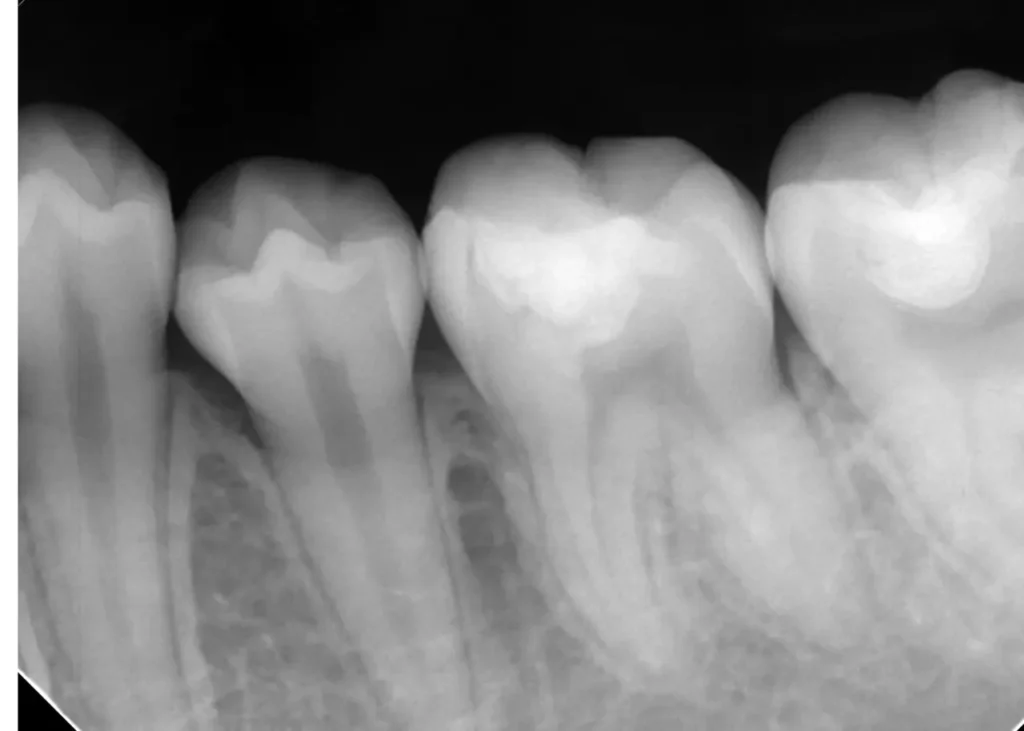

レントゲン写真

右の根の先に黒い影があります

5年後レントゲン写真

黒い影もすっかりなくなっています

治療後も予防歯科に通われ、予後良好です。